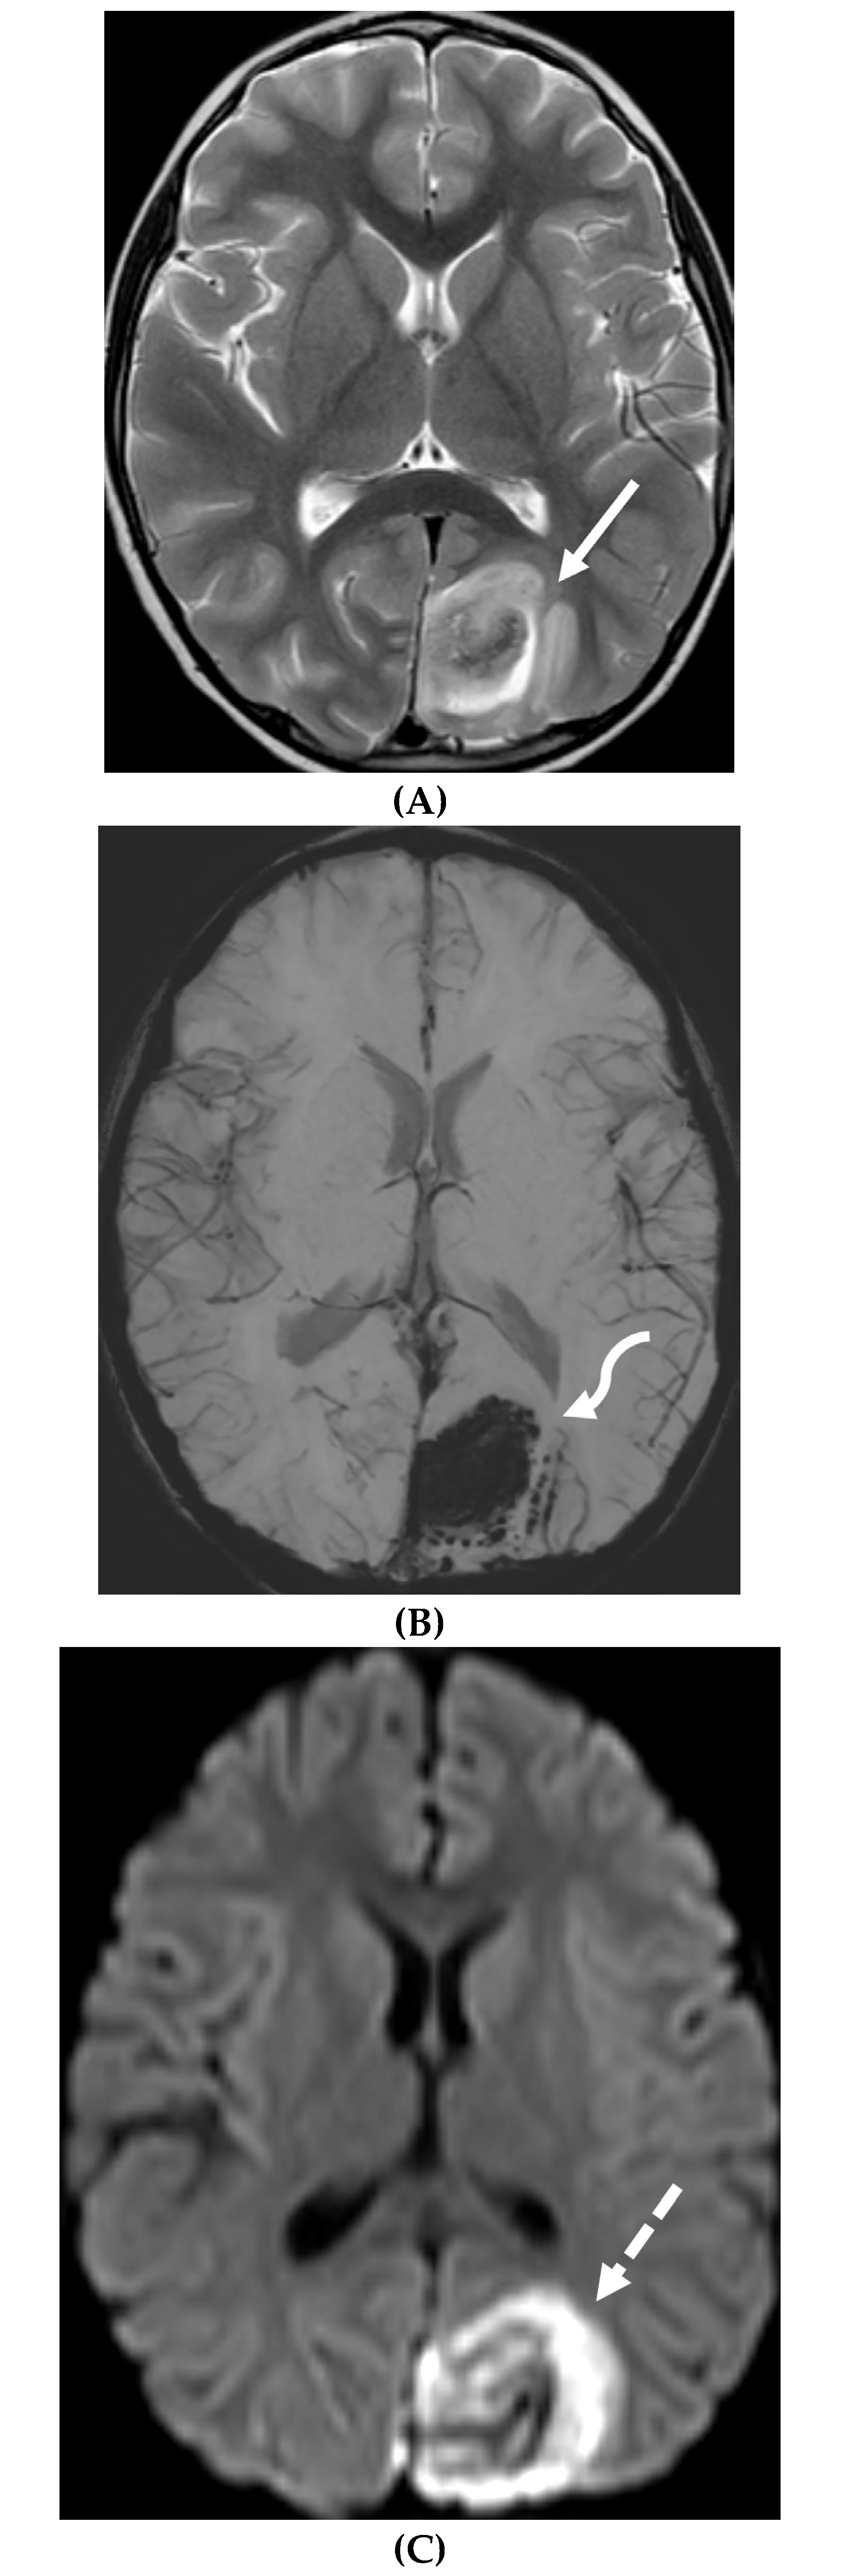

BACTERIAL MENINGITIS

- Vaswani AK, Nizamani WM, Ali M, Aneel G, Shahani BK, Hussain S. Diagnostic Accuracy of Contrast-Enhanced FLAIR Magnetic Resonance Imaging in Diagnosis of Meningitis Correlated with CSF Analysis. ISRN Radiol. 2014 Mar 20;2014:578986. PMID: 24977138; PMCID: PMC4062848. [CrossRef]

- Jaremko JL, Moon AS, Kumbla S. Patterns of complications of neonatal and infant meningitis on MRI by organism: a 10 year review. Eur J Radiol. 2011 Dec;80(3):821-7. Epub 2010 Nov 10. PMID: 21067879. [CrossRef]